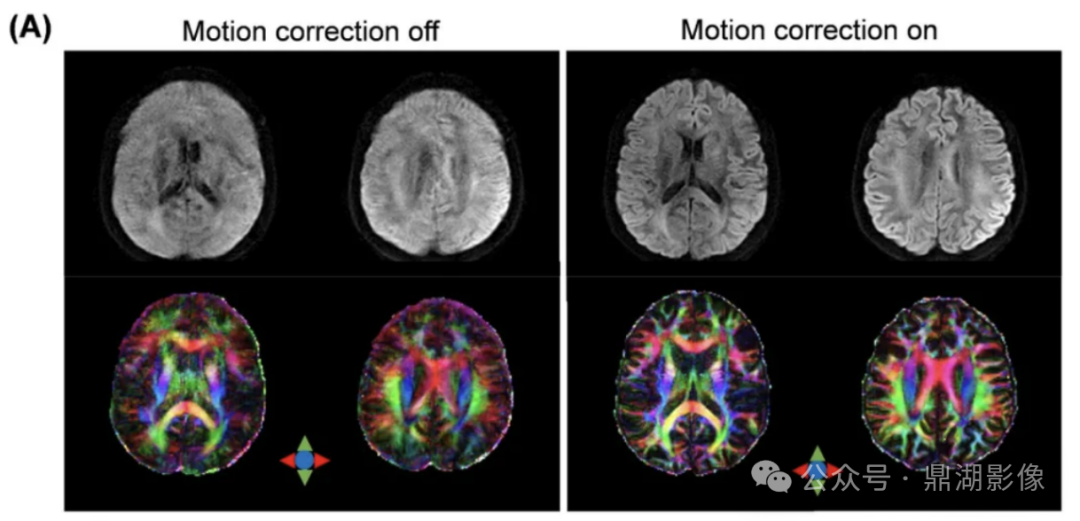

此外,搭载前瞻式头动校正功能可以通过3D红外结构光智能提取面部点云信息,实时捕捉和校正被试运动,保障脑科研数据精度与准确性。

(A)运动伪影实时矫正开启前后的弥散加权图像与方向编码彩色图谱对比,以及(B)ACS加速成像的示例。